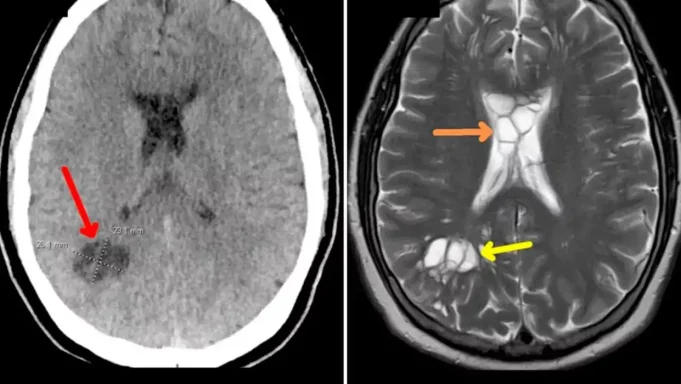

Nakon što je mjesecima trpio migrene muškarac je otišao kod doktora koji ga hitno poslao na snimanje glave. Na snimanju se ispostavilo kako je crv položio jaja u njegov mozak i iritirao tkivo ispod njegove lubanje.

Liječnici vjeruju da je parazit ušao u njegovo tijelo nakon što je konzumirao nedovoljno pečenu slaninu i putovao iz crijeva u mozak kroz krvotok.